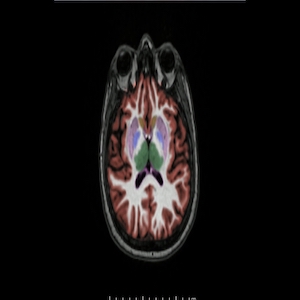

صورة من نوع من فحوص المسح الدماغي المعتمدة على التصوير بالرنين المغناطيسي (جرى تلوينها اصطناعيًا) تظهر دماغ شخص مصاب بمرض ألزهايمر.

من هنا، طور باحثون مؤخرًا تقنيات معتمدة على الذكاء الاصطناعي يمكن أن تساعد في حل هذه المشكلة. وأثبتت إحدى الخوارزميات فاعليتها في فرز عدد كبير من الصور الدماغية وتمييز الصور التي تظهر فيها الخصائص المميزة لمرض ألزهايمر. وتعتمد تقنية أخرى في هذا الإطار على تعلم الآلة وعلى تمييز سمات بنيوية مهمة في الدماغ، وهو ما قد يساعد العلماء في نهاية المطاف على رصد مؤشرات جديدة على مرض ألزهايمر في فحوص المسحي الدماغي.

في عام 2020، أطلق تومبسون اتحاد AI4AD، وهو ائتلاف يضم تحت لوائه باحثين من مختلف أنحاء الولايات المتحدة على طريق السعي إلى تطوير أدوات الذكاء الاصطناعي لتحليل ودمج البيانات الوراثية وبيانات فحوص التصوير الشعاعي وبيانات القدرات الإدراكية الخاصة بالمصابين بمرض ألزهايمر. وقد ضع الباحثون، في إطار هذا المشروع، نموذجًا معتمدًا على الذكاء الاصطناعي دُرب على تحليل عشرات الآلاف من صور المسوح الدماغية الملتقطة بتقنية التصوير بالرنين المغناطيسي، والتي كان أطباء قد اطلعوا عليها وانتقوا منها المسوح التي أظهرت شواهد دالة على المرض. ومن خلال هذه الصور، تعلمت أداة الذكاء الاصطناعي كيف تبدو أدمغة المصابين بالمرض مقارنًة بأدمغة غير المصابين به.